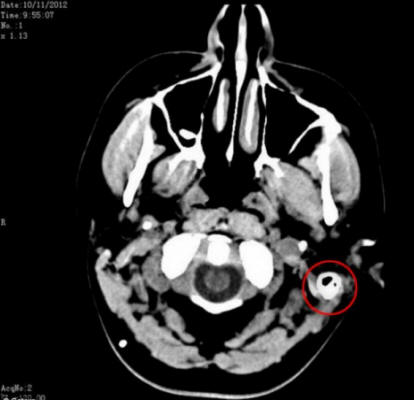

Ali nakon što su našli način da uklone suvišnu tečnost iz mozak joj je u stomak, život joj se promenio. Odvod, također poznat kao gastroperitonealni shunt, povezao je mozak i želudac, dozvoljavajući probavite moždanu tečnost i smanjite pritisak na mozak.

Sam je upućen na određeni broj profesionalaca koji su sumnjali su da možda ima tumor na mozgu. Srećom nakon sprovodeći niz testova izuzeta je tumor mozga lista mogućih uzroka bolesti. Međutim, ljekari to nisu uspjeli utvrditi šta joj se dogodilo. Stručnjaci su saznali istinu uzrok njenih zdravstvenih problema tek nakon lumbalne probijanje.

Ljudski mozak je okružen tečnošću koja štiti mozak od udaranja u zid lobanje, ali ispostavilo se da je Samino telo stvara ovu tekućinu tri puta više od norme. Ni poslije dijagnosticiranje i uzimanje 17 različitih lijekova dnevno, Sam i dalje patila od strašnih glavobolja.